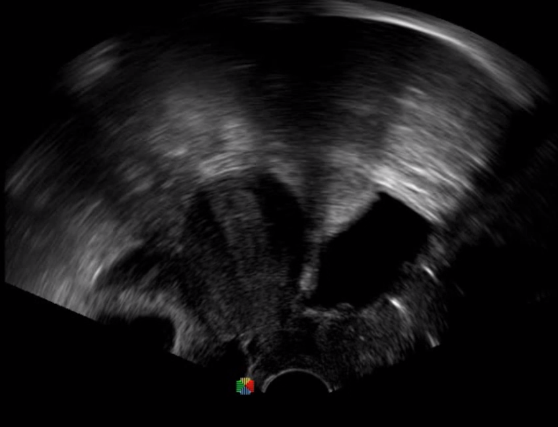

多數(shù)的生殖科醫(yī)生對于受精卵的植入采用憑經(jīng)驗操作或是使用傳統(tǒng)腔內(nèi)探頭引導,同樣存在手術(shù)空間小、受精卵放置位置不確定等風險。專業(yè)的宮腔專用探頭,配合專用的窺器使用,為醫(yī)生提供最大的手術(shù)視野。

胎移植臨床圖